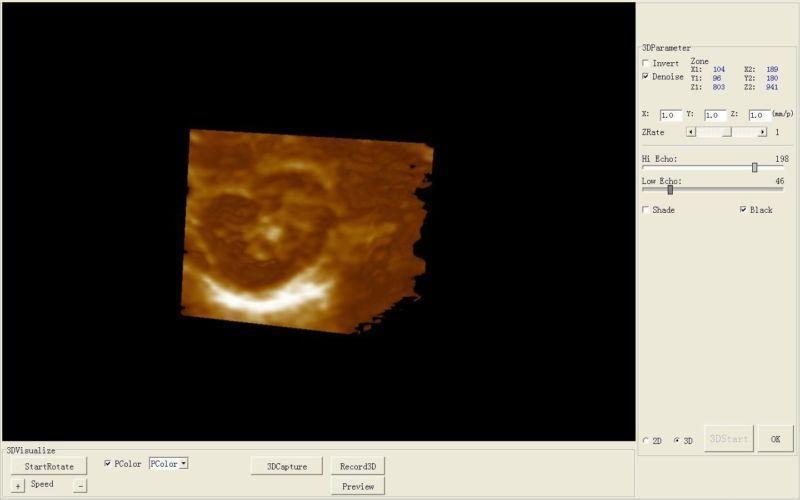

Permanent Storage: 1024: Abdomen (Distance, circumference, area, volume)